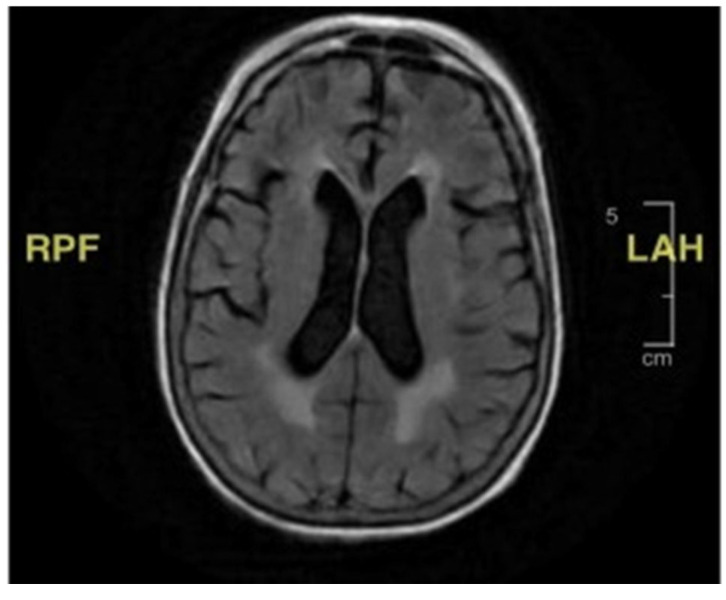

Background/Objectives: Lower-extremity weakness in older adults is often overlooked, yet it can have reversible or medical causes that contribute to increased falls. Common factors include vision disturbances, impaired balance due to otolith dysfunction, arthritis-related immobility, and lower-extremity neuropathy. This case presents a unique diagnostic challenge in evaluating bilateral lower-extremity weakness and recurrent falls in an older adult, highlighting the complexity of diagnosing conditions with overlapping symptoms. Case Presentation: The patient, a woman with a history of a neuroendocrine tumor, experienced progressive weakness in her lower extremities, along with oculomotor and facial muscle involvement, despite extensive testing. Key clinical findings included elevated protein levels in cerebrospinal fluid, suggesting the possibility of an infectious or autoimmune process. A thorough investigation was conducted, including testing for both common and rare conditions such as Guillain-Barré syndrome, Lyme disease, and tuberculosis. Results: Despite comprehensive diagnostic efforts, no clear etiology was identified. The patient's condition was eventually considered to be related to carcinomatosis meningoencephalitis, a rare complication from a previous cancer diagnosis. Given the progressive nature of her symptoms and lack of treatment options, she was transitioned to palliative care. Conclusions: This case highlights the importance of a comprehensive differential diagnosis in older patients with unexplained weakness and falls. Rare neurological conditions should not be overlooked, even when more common causes are suspected. Clinicians should remain aware that falls and weakness in older adults may stem from various pathologies, some of which are reversible if identified early, and rare causes must always be considered when standard treatments fail.